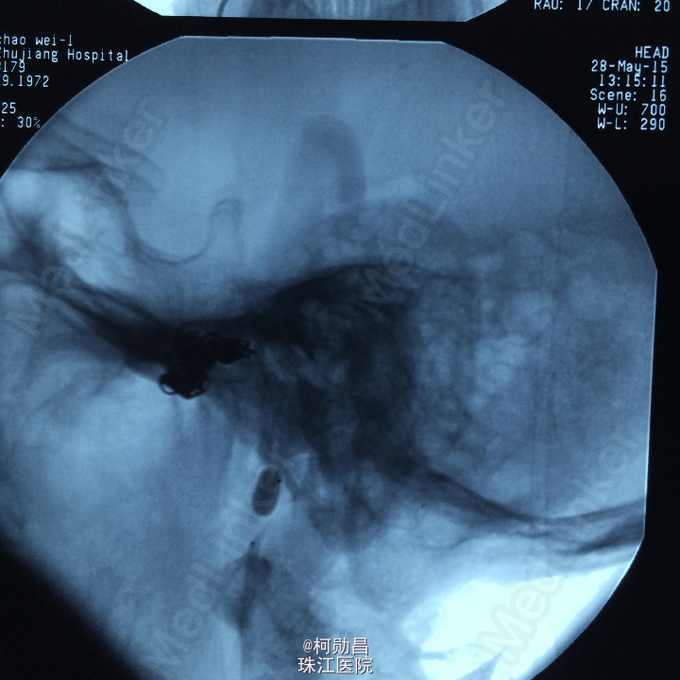

诊断:颈内动脉假性动脉瘤破裂 处理:急诊行DSA检查,提示颈内动脉海绵窦段动脉瘤形成并破裂向鼻腔引流,予血管内栓塞治疗,将动脉瘤腔堵塞,患者出血停止。